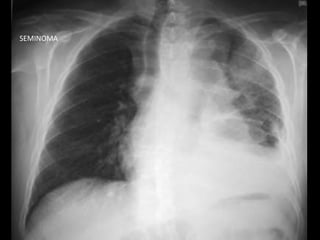

SEMINOMAS

• Ubicación: mediastino anterior

• Edad: 30 años

• Clínica: por efecto de masa

• Diagnóstico:

– PAAF

– GCH aumentada en 10%

– Alfafetoproteína siempre negatina

• Tratamiento: QTX + RTX + cirugía de lesiones residuales con

excelente respuesta

SEMINOMAS • Ubicación: mediastinoanterior • Edad: 30 años • Clínica: por efecto de masa • Diagnóstico: – PAAF – GCH aumentada en 10% – Alfafetoproteína siempre negatina • Tratamiento: QTX + RTX + cirugía de lesiones residuales con excelente respuesta